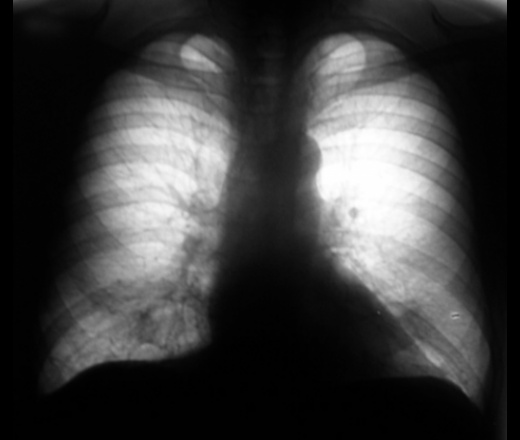

Динамика через 1,5 года.

На перый снимках двусторонняя инфильтрация (пневмония?), на последних похоже на формирующийся абсцесс в левом легком.

На первых снимках, ретроспективно, смутило повышение прозрачности левого легочного поля.

А за счет чего появилась гипервоздушность левого легкого?

С другой стороны, если бы это был рак с обструкцией бронха, то при таком размере опухоли и при том что 1.5 года назад уже было частичное нарушение проходимости, сейчас наверное бы было уже выраженное нарушение вентиляции легкого. А на рентгенограммах вроде гиповентиляции нет - легочный рисунок не сгущен, купол диафрагмы стоит на месте.

#18, рис. 2. - четкие признаки нарушения бронхиальной проходимости (смещение тени средостения в сторону поражения, левый купол диафрагмы выше правого, повышение воздушности правого легкого). Пока мнение мое остается прежним, однако не нравится окружающий фон (очаговость?). Дело за другими методами исследования. Можно поискать и палочки Коха, но локализация не очень подходит. Хотя, на сайте простых клинических наблюдений не бывает Жду.

Жизнь и динамика показала, что не просто "рачок", а рак лёгкого во всем великолепии.

за очередное замечательное клиническое наблюдение. Признаки неравномерной вентиляции легких у Мужчин старше 50 лет должны быть поводом для обследования на рак . Это и будет настоящее ранее выявление карциномы бронха. С уважением Nikolas.

То есть действительно вырос такой большой рак с распадом, или была маленькая опухоль, обтурирующая бронх, с пневмонией?